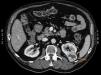

Paraneoplastic erythema annulare centrifugum eruption (PEACE)

Eritema anular centrífugo paraneoplásico (PEACE)